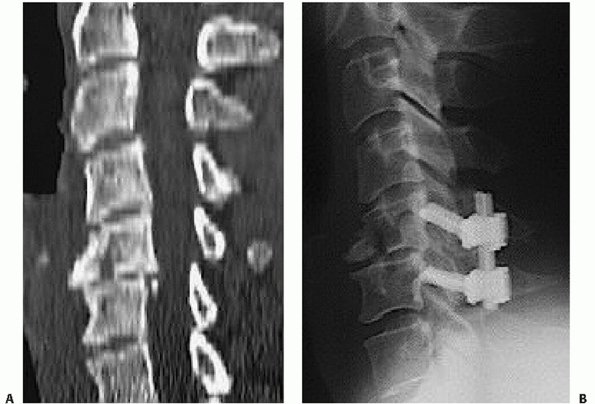

understanding the three-dimensional nature of spinal injuries.

Paramedian slices through the facet joints can help visualize

dislocations, subluxations, or fracture fragment size (Fig. 42-13).

Canal occlusion is best appreciated on mid-sagittal CT reconstructions.

Widening of the occipitoatlantal joints and occipital condyle fractures

are best appreciated on coronal and sagittal images.

![]() |

|

FIGURE 42-12

Frank dislocation is usually obvious on axial CT images, as in this case of a C6-C7 fracture dislocation. More subtle amounts of translation, however, can be easily missed using axial CT images alone. |

FIGURE 42-13

Paramedian CT reconstructions are useful for assessing the facet joints. In this case, a C4-C5 unilateral facet perch can be appreciated. |